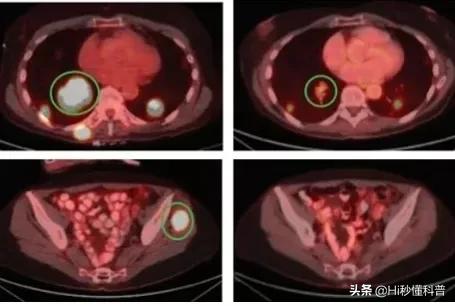

一位68岁的女士,在2017年确诊了NTRK融合晚期甲状腺癌,她接受全身化疗。在2019年2月开始使用瑞波替尼,直到第6个星期肿瘤缩小了68%。